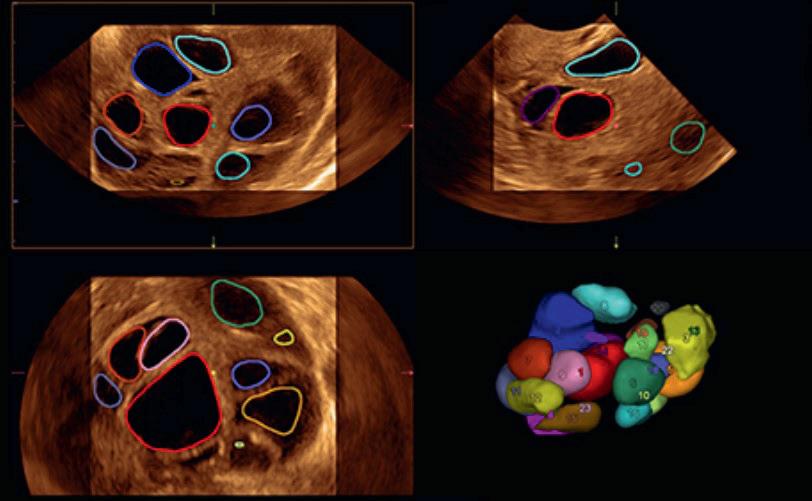

Kurset dekket et bredt spekter av temaer innenfor tidlig svangerskap. Et foredrag som ble veldig godt mottatt var Jackie Ross foredrag om identifisering av tubare ektopiske svangerskap med ultralyd. Flere videoer viste oss nøyaktig hvordan man følger tubene fra interstitium frem til fimbria, både når tubene inneholder et svangerskap og for normale tuber. Dr. Ross viste også eksempler på hvordan endometrium kan se ut ved ektopiske svangerskap, samt tips for å finne et tubart svangerskap.

Dr. Eline Seljeflot, overlege på St. Olavs beskrev steg-for-steg hvordan man bruker 3D-ultralyd med illustrative videoer og bilder. Det var et veldig nyttig og verdifullt foredrag for de 92% av deltagerne som ikke bruker 3D-ultralyd regelmessig.